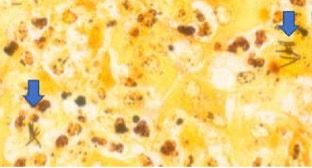

Microscopisch bleek het leverweefsel doorzaaid met necropurulente ontstekingshaardjes, waardoor ongeveer 40 procent van het leverparenchym verloren was gegaan. Aan de periferie van deze ontstekingshaardjes vertoonden de hepatocyten coagulatienecrose, in de meer centrale gedeelten lytische necrose, waardoor in het centrum van de ontstekingshaardjes alleen nog het reticulaire netwerk aanwezig was (figuur 1). Over het algemeen was rond de centraalvenen nog een smalle zoom van intact parenchym aanwezig. In de HE-kleuring werden geen virale insluitlichaampjes waargenomen. Voor zover het leverparenchym intact was, waren hier aanwijzingen voor hydropische degeneratie. Immunohistochemisch onderzoek op leptospirose en EHV1/EHV4 verliep negatief. Omdat de ziekte van Tyzzer onderdeel uitmaakt van de histopathologische differentieeldiagnose, is een aanvullende Warthin-Starry zilverkleuring uitgevoerd. Door middel van deze kleuring werd de aanwezigheid aangetoond van argyrofiele, naaldvormige intracellulaire bacteriën die de neiging hadden bundels te vormen, in de hepatocyten aan de periferie van de necrosehaardjes (figuur 2). Deze histopathologische bevindingen zijn pathognomonisch voor de ziekte van Tyzzer. Verder was in de cortex van de grote hersenen sprake van uitgebreid perivasculair oedeem, uitgebreide degeneratie van neuronen, verspreid acute necrose van neuronen en intracellulair oedeem in astrocyten. Deze microscopische veranderingen passen, in combinatie met de hierboven beschreven veranderingen in het leverweefsel, bij  hepato-encefalopathie. Dit verklaart de klinisch waargenomen neurologische verschijnselen.

Figuur 2. Microscopisch beeld van het leverweefsel. Naaldvormige, zwart aankleurende (argyrofiele) intracellulaire bacteriën in necrotische hepatocyten (pijl). De vorm en rangschikking van deze bacteriën is kenmerkend voor Clostridium piliforme (voorheen Bacillus piliformis genoemd). Warthin Starry zilverkleuring.